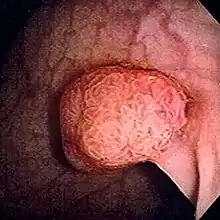

| Polyp of sigmoid colon as revealed by colonoscopy. Approximately 1 cm in diameter. The polyp was removed by snare cautery. | |

In anatomy, a polyp is an abnormal growth of tissue projecting from a mucous membrane. If it is attached to the surface by a narrow elongated stalk, it is said to be pedunculated; if it is attached without a stalk, it is said to be sessile. Polyps are commonly found in the colon, stomach, nose, ear, sinus(es), urinary bladder, and uterus. They may also occur elsewhere in the body where there are mucous membranes, including the cervix, vocal folds, and small intestine. Some polyps are tumors (neoplasms) and others are non-neoplastic, for example hyperplastic or dysplastic, which are benign. The neoplastic ones are usually benign, although some can be pre-malignant, or concurrent with a malignancy.

While colon polyps are not commonly associated with symptoms, occasionally they may cause rectal bleeding, and on rare occasions pain, diarrhea or constipation.[9] They are a concern because of the potential for colon cancer being present microscopically, and the risk of benign colon polyps becoming malignant over time.[10] Since most polyps are asymptomatic, they are usually discovered at the time of colon cancer screening. Common screening methods are occult blood test, colonoscopy with a modern flexible endoscope, sigmoidoscopy (usually with the older rigid endoscope), lower gastrointestinal series (barium enema), digital rectal examination (DRE), virtual colonoscopy or Cologuard.[11] The polyps are routinely removed at the time of colonoscopy, either with a wire loop known as a polypectomy snare (first description by P. Deyhle, Germany, 1970),[12] or with biopsy forceps. If an adenomatous polyp is found, it must be removed, since such a polyp is pre-cancerous and has a propensity to become cancerous. For certainty, all polyps which are found by any diagnostic modality, are removed by a colonoscopy. Although colon cancer is usually not found in polyps smaller than 2.5 cm, all polyps found are removed since their removal reduces the likelihood of future colon cancer. When adenomatous polyps are removed, a repeat colonoscopy is usually performed three to five years later.

The risks of progression to colorectal cancer increase if the polyp is larger than 1 cm and contains a higher percentage of villous component. Also, the shape of the polyps is related to the risk of progression into carcinoma. Polyps that are pedunculated (with a stalk) are usually less dangerous than sessile polyps (flat polyps). Sessile polyps have a shorter pathway for migration of invasive cells from the tumor into submucosal and more distant structures, and they are also more difficult to remove and ascertain. Sessile polyps larger than 2 cm usually contain villous features, have a higher malignant potential, and tend to recur following colonoscopic polypectomy.[18]